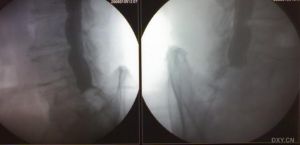

體格檢查除腰骶部有壓痛及叩擊痛外,一般無陽性體徵。血沉及抗“0”均為正常。X線檢查亦無異常發現,有時可有腰骶椎的退行性改變。